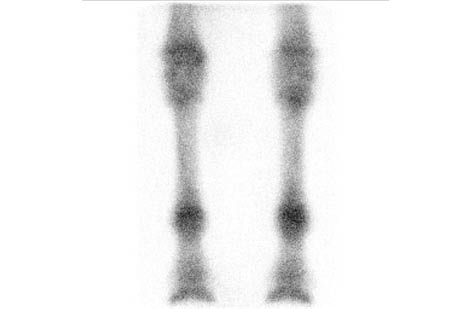

Motion Correction on the Fly

Innovative Imaging Technology

To minimize motion artifacts for the standing horse, MiE has developed the world’s first real-time motion correction. The rigid registration software allows shorter image acquisition times and improved diagnostic quality. Using the ParalyzerPLUS software eliminates the need to repeat acquisitions.

Real-Time Motion Correction: Faster Scans, Enhanced Quality

ParalyzerPLUS

ParalyzerPLUS raw study

raw study ParalyzerPLUS

ParalyzerPLUS raw study

raw study ParalyzerPLUS

ParalyzerPLUS raw study

raw study ParalyzerPLUS

ParalyzerPLUS raw study

raw studySelection of possible studies